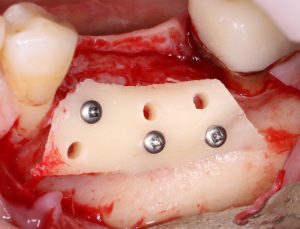

известная всем пластика костным блоком — не что иное, как аутотрансплантация крупного костного фрагмента:

мембранная аугментация — один из вариантов каркасной методики НКР с резорбируемым каркасом:

а использование титановой сетки — та же НКР, но уже каркасная нерезорбируемая:

И, наконец, «ламинарная техника»:

и прочие «сендвичи»:

являются примерами комбинированных методик, сочетающих в себе как пересадку крупного костного фрагмента, так и использование резорбируемой каркасной НКР.